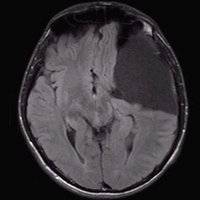

Arachnoidalzyste

Arachnoidalzyste T1 coronar